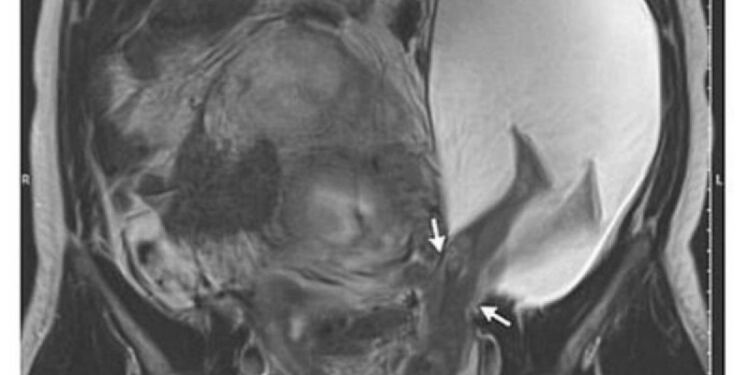

Συγκεκριμένα, μια έγκυος γυναίκα στην Κίνα σώθηκε χάρη στους γιατρούς, αφού το αγέννητο μωρό της κλώτσησε τη μήτρα της σε μια “εξαιρετικά σπάνια” περίπτωση.

Η αγέννητη κόρη της κ. Ζανγκ λέγεται ότι κλώτσησε την ίδια τόσο σκληρά, που έσκαψε μια πληγή στον τοίχο της μήτρας της, η οποία είχε μείνει από μια προηγούμενη εγχείρηση.

Το κοριτσάκι γεννήθηκε στις 35 εβδομάδες με καισαρική τομή και η ίδια αλλά και η μητέρα της βρίσκονται σε σταθερή κατάσταση, σύμφωνα με το Νοσοκομείο Shenzhen του Πανεπιστημίου του Πεκίνου στη νότια Κίνα.